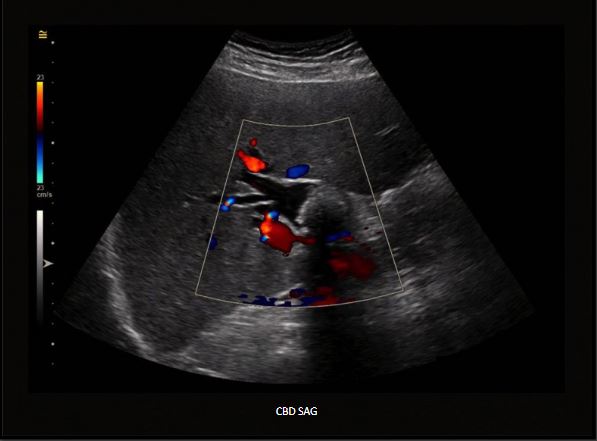

A patient with right upper quadrant pain, nausea, and vomiting presented for an ultrasound evaluation. IMAGING FINDINGSThe right upper quadrant ultrasound revealed a large shadowing structure in the abnormally dilated proximal CBD with associated intrahepatic biliary duct dilatation. Findings suggest a large CBD stone vs. partially calcified mass.

FINAL DIAGNOSIS: Large CBD stone (choledocholithiasis).CBD SAGCholedocholithiasis is a condition defined by the presence of stones within the common bile duct (CBD). Depending on the stone origin, choledocholithiasis is classified as primary or secondary. When the stones are formed directly within the biliary tree, the condition is referred to as primary choledocholithiasis. In contrast, the condition is called secondary choledocholithiasis, when the stones are formed in the gallbladder and ejected into the biliary tree following the gallbladder contractions.Primary choledocholithiasis is typically composed of brown stones and is rare in Western populations. Brown stones are commonly found in the extrahepatic and intrahepatic ducts in the presence of biliary stasis and bacterial infection. Bacterial by-products in the bile stasis environment cause precipitation of bilirubin out of solution, leading to a formation of brown stone. Secondary choledocholithiasis is the most common form of the condition. It results from the passage of stones formed in the gallbladder into the cystic duct and then into the common bile duct. These stones are typically composed of cholesterol. 95

As mentioned earlier, in the vast majority of choledocholithiasis cases, the stones form within the gallbladder and then migrate into the CBD due to gallbladder contractions. Once lodged in the CBD, the stones may disrupt the normal bile flow and cause various problems, including severe right upper quadrant pain, nausea, vomiting, biliary obstruction, and jaundice. Biliary obstruction and stagnant bile may lead to the colonization of bile by microorganisms resulting in bile infection and consequent ascending cholangitis. CBD SAGA large shadowing structure in the abnormally dilated proximal CBD with associated intrahepatic biliary duct dilatation represents choledocholithiasis.96

A confirmatory diagnosis of choledocholithiasis is made with advanced imaging, including magnetic resonance cholangiopancreatography (MRCP) and endoscopic retrograde cholangiopancreatography (ERCP). A transabdominal ultrasound is typically the first imaging test that is ordered for the patient suspected of any biliary disease. Like gallbladder stones, biliary stones appear echogenic and round-shaped. They often cast dense posterior acoustic shadowing and can be mobile. Unfortunately, ultrasound is significantly less accurate in detecting stones in the CBD than detecting stones in the gallbladder.CBD SAGAbnormally dilated CBD measuring up to 3 cm with approximately 2.6 cm shadowing structure identified centrally is choledocholithiasis.97